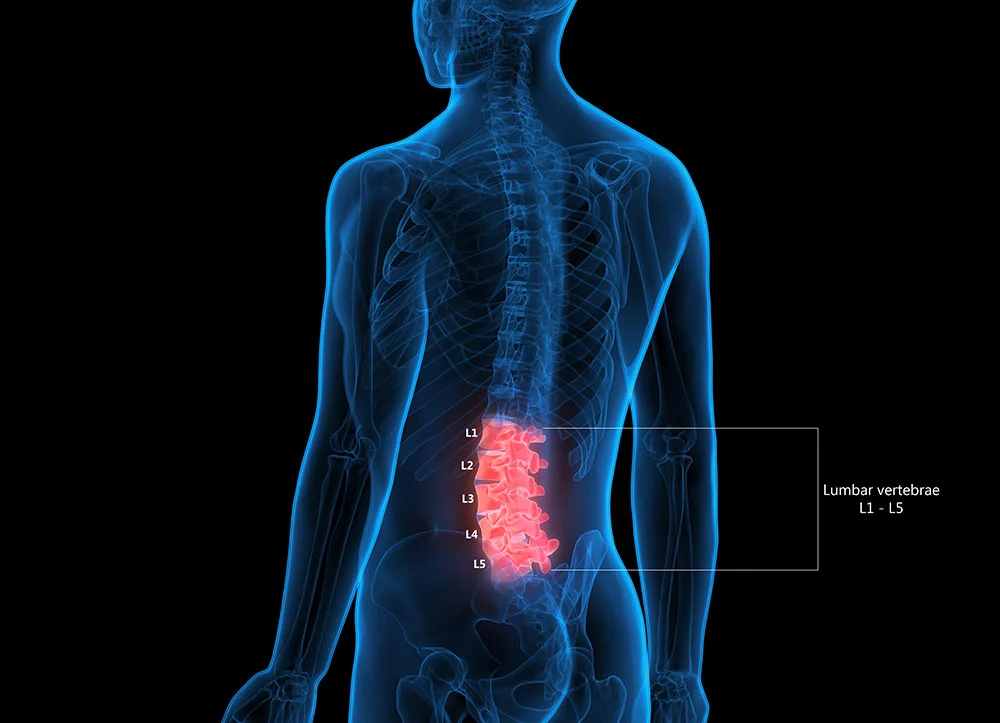

دیسک کمر و علت درد

دیسکها ساختارهای ژلاتینی بین مهرههای ستون فقرات هستند که نقش ضربهگیر و انعطافپذیری ستون فقرات را دارند. با افزایش سن، فشارهای مکرر یا آسیبهای ناگهانی، دیسکها دچار آسیب، ترک یا بیرونزدگی میشوند. این بیرونزدگی یا فتق دیسک ممکن است روی ریشههای عصبی فشار وارد کند و موجب درد، بیحسی و ضعف عضلانی شود.